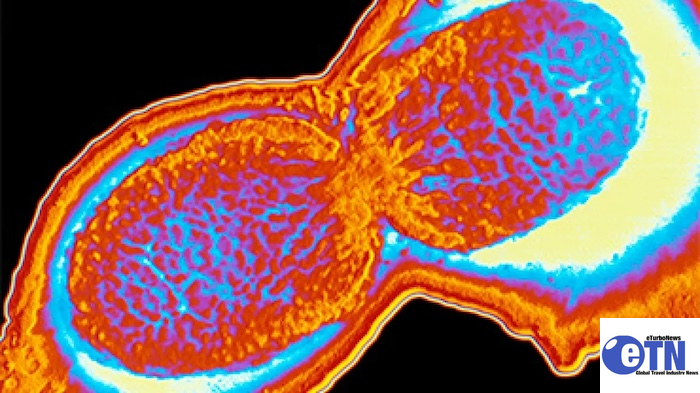

According to lawyers representing the claimants, travelers reported a range of serious gastrointestinal illnesses during or after their stays in Cape Verde. These include infections caused by Salmonella, E. coli, and Shigella bacteria, as well as various parasitic diseases.

Epidemiological update: Shigellosis and other gastrointestinal infections in travelers returning from Cabo Verde

As of March 2026, over 1 000 confirmed and possible cases of shigellosis and other gastrointestinal infections, including salmonellosis, have been detected in travelers returning from Cabo Verde to several countries in the European Union/European Economic Area (EU/EEA), the United Kingdom (UK), and the United States (US), with new cases still being reported.